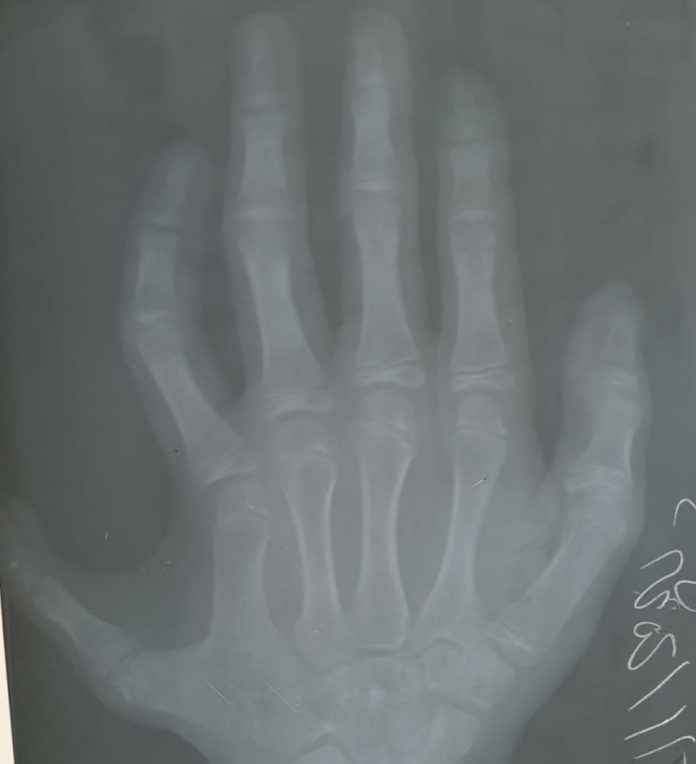

Pyetje: Jam furnizuar me (lindjen e) një vajze që ka një gisht të gjashtë në dorën e saj të majtë. Cili është gjykimi i Islamit për heqjen e tij?